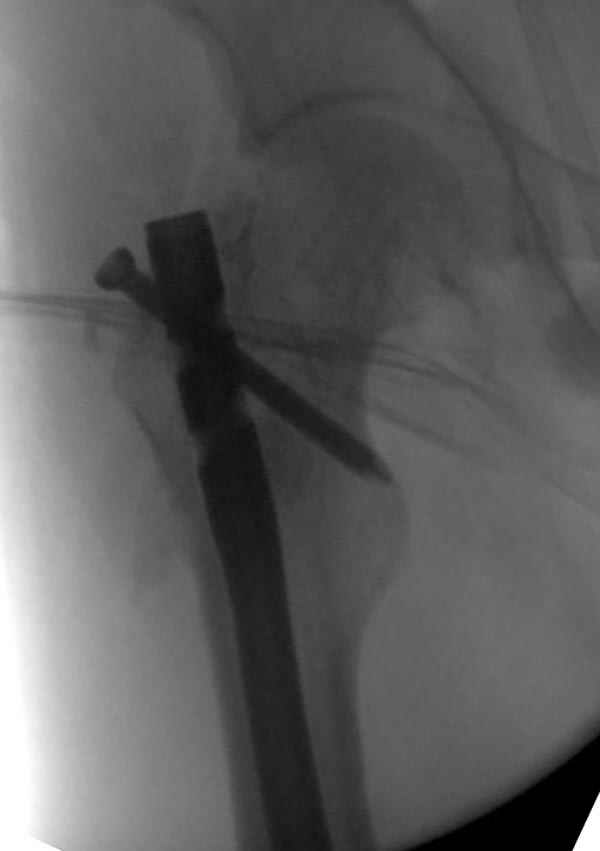

Рутинный интрамедуллярный остеосинтез с расверливанием и с фиксацией реконструктивным трокантерик штифтом (рис №1, №2),

если первые 4 месяца послеоперационного периода проходил без проблем, но на 5 месяце появились боли в дистальном отделе бедра и температура, т.е. симптомы медуллярного инфицирования (рис №3, №4).

Замена реконструктивного штифта “Custom made Nail” с антибиотиком (рис №5, №6),

после промывки канала с рассверливанием внутреннего кортекса, через 4 недели антибиотический штифт удалили, оспалителный процесс остановлен и бедро сросся.